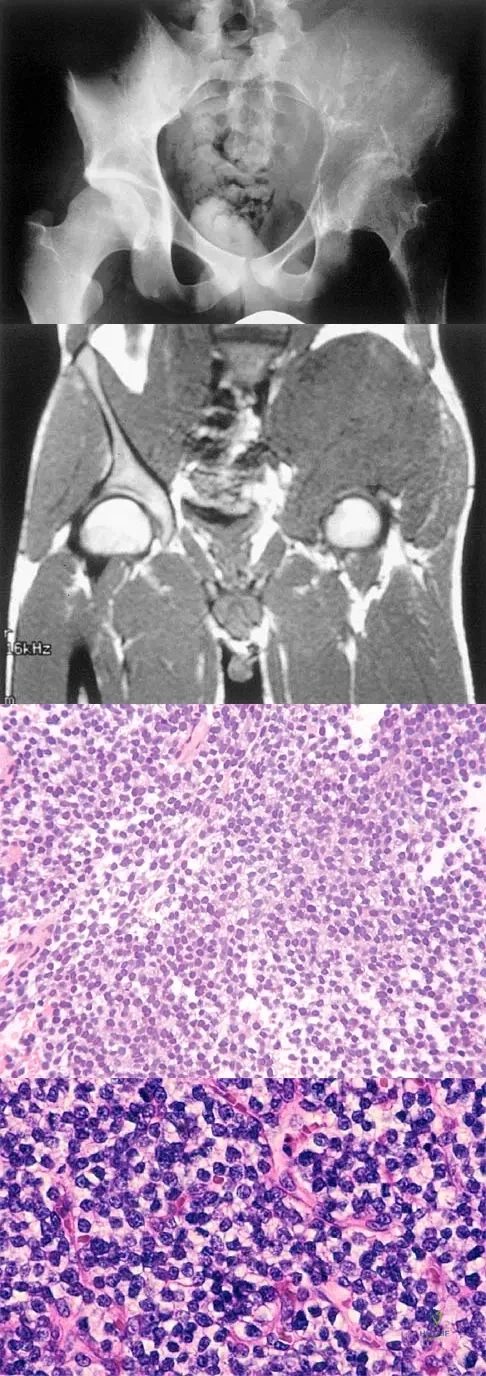

Question 19

A 25-year-old man has had an insidious onset of left hip pain over the past 11 months. A radiograph, coronal MRI scan, and histopathologic specimens are seen in Figures 2a through 2d. What is the most likely diagnosis?

Explanation